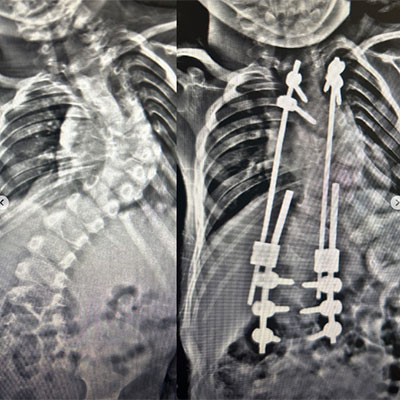

Revizyon Ameliyatı

Erken başlangıç gösteren skolyozlarda ve konjenital (doğumsal ) skolyozlarda tekrar gerektiren operasyonlar yapılır. Ayrıca enfeksiyon, enstrüman (implant ) hataları, psödoartroz (kaynama sorunları )ya da tamamlanmamış cerrahi işlem durumlarında revizyon cerrahisi uygulanmalıdır.Yani; mekanik sorunlar,komplikasyonlar,enfeksiyon ve zaman içinde gelişen büyüme yada yaşlanma sorunları nediyle revizyon gerektiren skolyoz ve kifoz hastalarına kliniğimizde tecrübeli ekip dahilinde cerrahi müdahaleler gerçekleştirilmektedir .